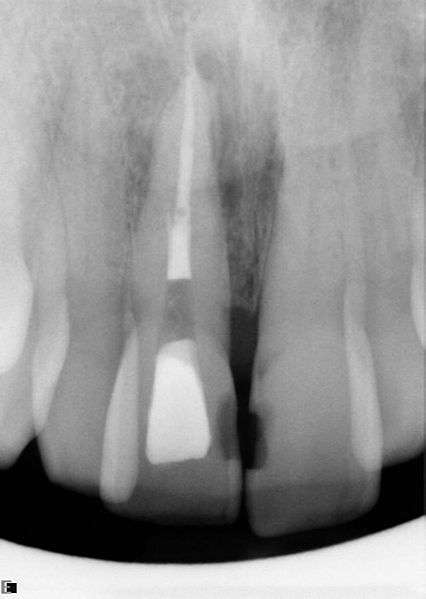

Root Canal Treatment: How Much Good Health Do You Have to Give Away?

The text below is the IABDM’s current position paper on root canal treatment by Dr. Dawn Ewing. You can access other position papers, as well as our standards of practice […]